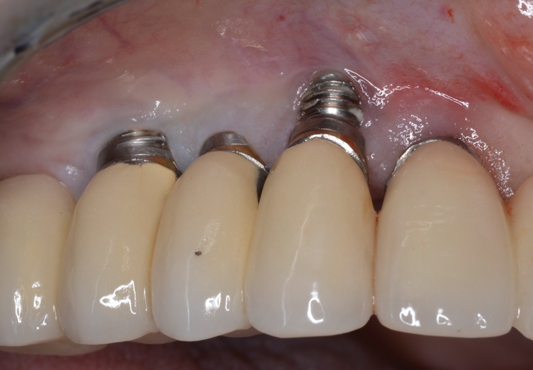

Fig 5. A 35-year-old patient with a missing central incisor due to trauma was restored with an implant (Fig 5, day of second-stage surgery). Twelve years later she presented to the office complaining that pus was draining from the implant and she felt uncomfortable. As can be seen in Fig 6, severe peri-implant bone loss due to peri-implantitis was evident.

Fig 6. A 35-year-old patient with a missing central incisor due to trauma was restored with an implant (Fig 5, day of second-stage surgery). Twelve years later she presented to the office complaining that pus was draining from the implant and she felt uncomfortable. As can be seen in Fig 6, severe peri-implant bone loss due to peri-implantitis was evident.